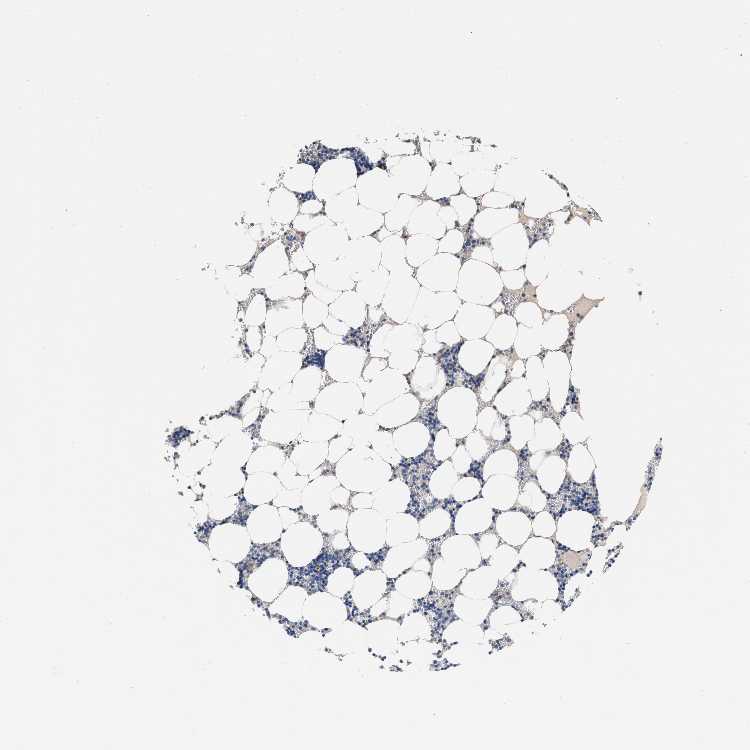

TISSUE PRIMARY DATA BONE MARROW Show tissue menu

BONE MARROW - Antibody stainingi

Antibody staining in the annotated cell types in the current human tissue is reported as not detected, low, medium, or high, based on conventional immunohistochemistry profiling in selected tissues. This score is based on the combination of the staining intensity and fraction of stained cells.

Each image is clickable and will lead to virtual microscopy that enables deeper exploration of all samples and also displays staining intensity scores, fraction scores and subcellular localization as well as patient and tissue information for each sample.

Antibody HPA021165Antibody HPA021753Antibody HPA021760

Hematopoietic cells Not detectedNot detectedNot detected